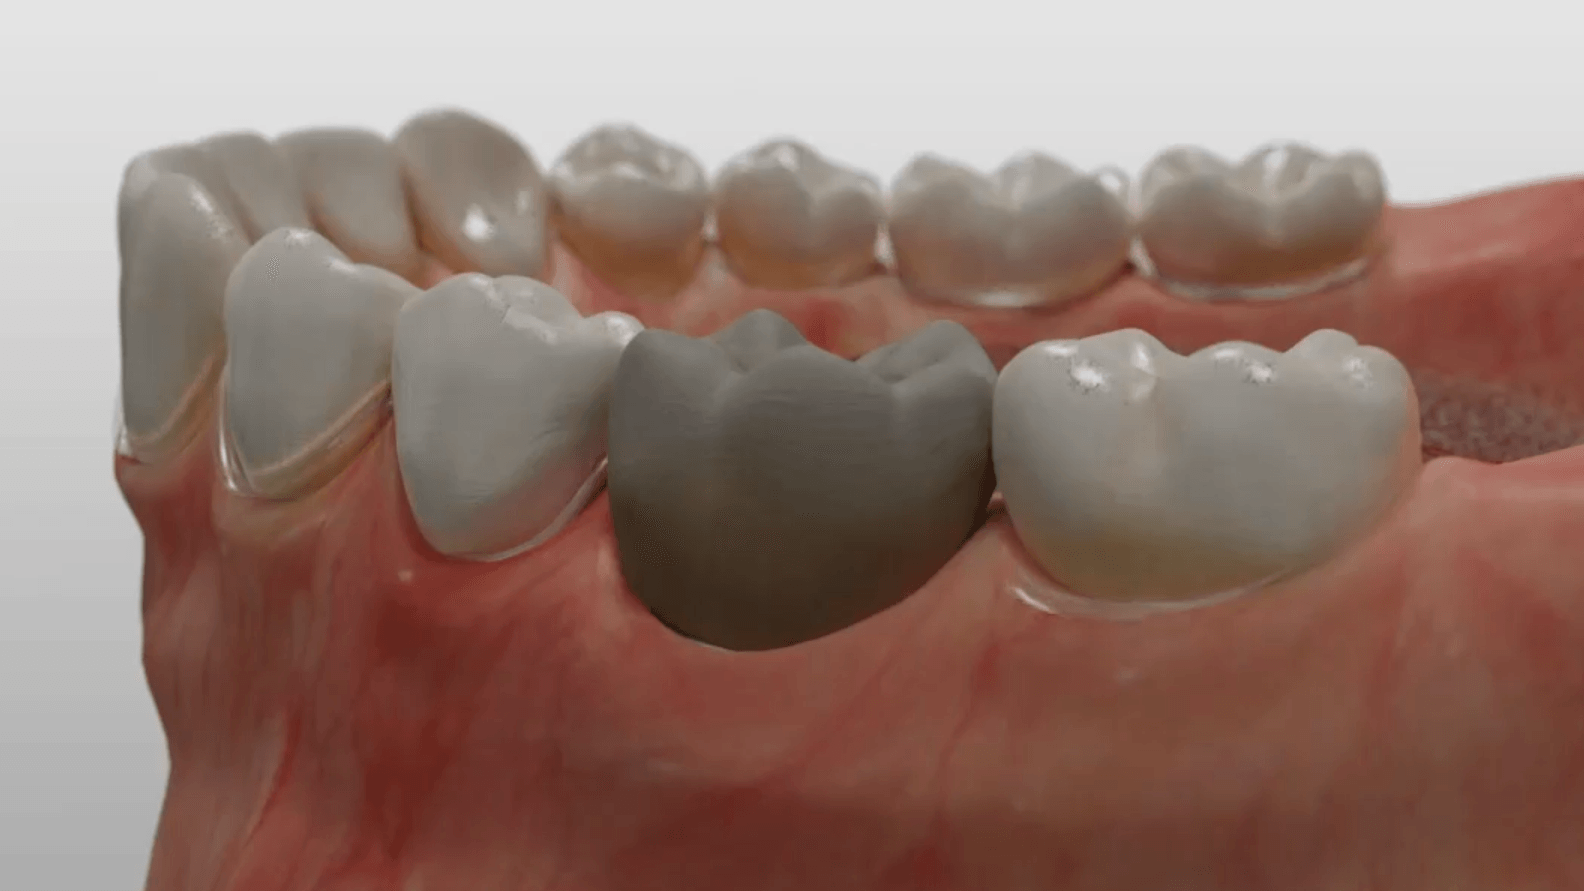

Durch den Verlust des Zahnes wandelt sich der Kieferknochen um. Nach der oberflächlichen Heilung wird das knöcherne Zahnfach vom Körper rasch abgebaut. Knochen ist für den Körper ein "teures" Gewebe, und ohne die funktionelle Kaubelastung durch einen Zahn gibt es für den Körper keinen Grund mehr, das knöcherne Zahnfach zu erhalten. Allein im ersten Jahr nach der Zahnentfernung gehen 50% des umgebenden Knochens verloren! Das ist insbesondere dann von Nachteil, wenn geplant ist, später ein Implantat für den Ersatz des Zahnes zu setzen. Ohne kiefererhaltende Maßnahmen reicht oftmals der nach der Heilung verbliebene Knochen nicht mehr aus, ein hinreichend großes Implantat einzusetzen bzw. dieses auch ideal zu positionieren.

Aus diesem Grund werden seit vielen Jahren

Knochenersatzmaterialien aus tierischem, pflanzlichen oder mineralischen Ursprung verwendet, um die Schrumpfung des Kieferknochens aufzuhalten und dadurch die ursprünglichen Dimensionen zu bewahren.